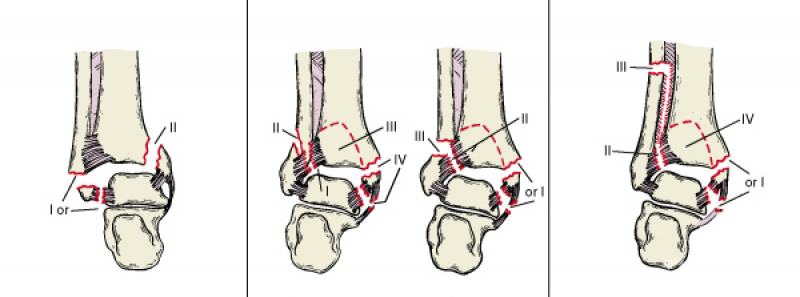

Danis-Weber分型是按外踝骨折部位与下胫腓联合关系来作为分类标准(图2)。

A型:外踝骨折线在踝关节和下胫腓联合以下,下胫腓联合韧带和三角韧带未损伤。如附有内踝骨折,骨折线几乎呈垂直,是由于距骨内翻力所致。

B型:外踝在下胫腓联合平面骨折,多伴有内踝骨折或三角韧带损伤,由距骨的外旋力所致。

C型:腓骨在下胫腓联合近侧骨折,伴下胫腓联合韧带损伤,或伴三角韧带损伤或内踝骨折。

图2 踝关节骨折的Danis-Weber分型

Lauge-Hansen分型是以踝关节骨折的受伤机制和病理生理为基础(图3)。

Lauge-Hansen根据尸体解剖和临床实践研究,把踝关节损伤时外力作用的方向,足所处的位置结合起来提出了Lauge-Hansen分型法。每型的前半指受伤时足所处的位置—旋前或旋后,后半部分则指外力的方向—外旋、外展或内收。

图3 踝关节骨折的Lauge-Hansen分型